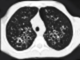

77.患者,男,29岁。咳嗽、咳痰、咯血多年,CT如图,最可能的诊断为()